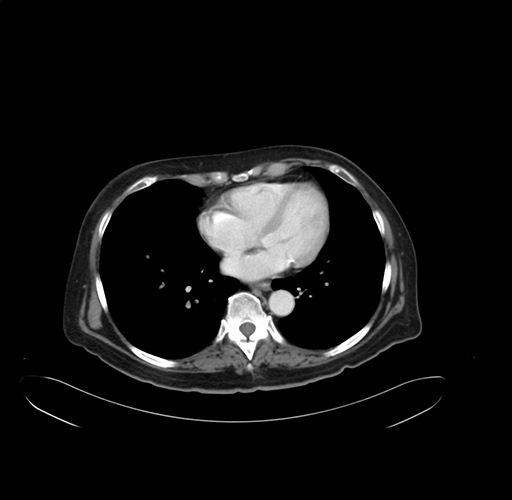

Pre-Chemo: Axial Venous